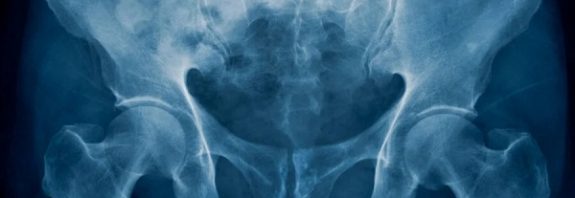

What makes us human? It’s all in the hips

What makes us human? It’s all in the hips New study shows how pelvis evolved for walking upright, allowing birth … Continue reading What makes us human? It’s all in the hips